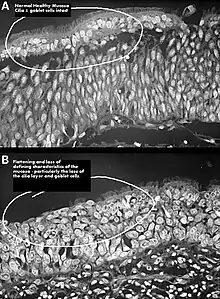

One possible cause may be changes to the nasal mucous membrane and to the nerve endings in the mucosa resulting from chronic changes to the temperature and humidity of the air flowing inside the nose, caused in turn by removal or reduction of the turbinates.[3][5] Direct damage to the nerves may be a result of surgical intervention; however, as of 2015, there is no technology that allows the mapping of the sensory nerves within the nose, so it is difficult to determine whether this is causative of ENS.[3] Investigators have been unable to identify consistent diagnostic or precipitating features, psychological causes leading to a psychosomatic condition have been proposed.[3][9][10][12]

- ENS-type: Patient appears to have adequate turbinate tissue but suffers ENS symptoms due to damage to the mucosal surface of the turbinates.